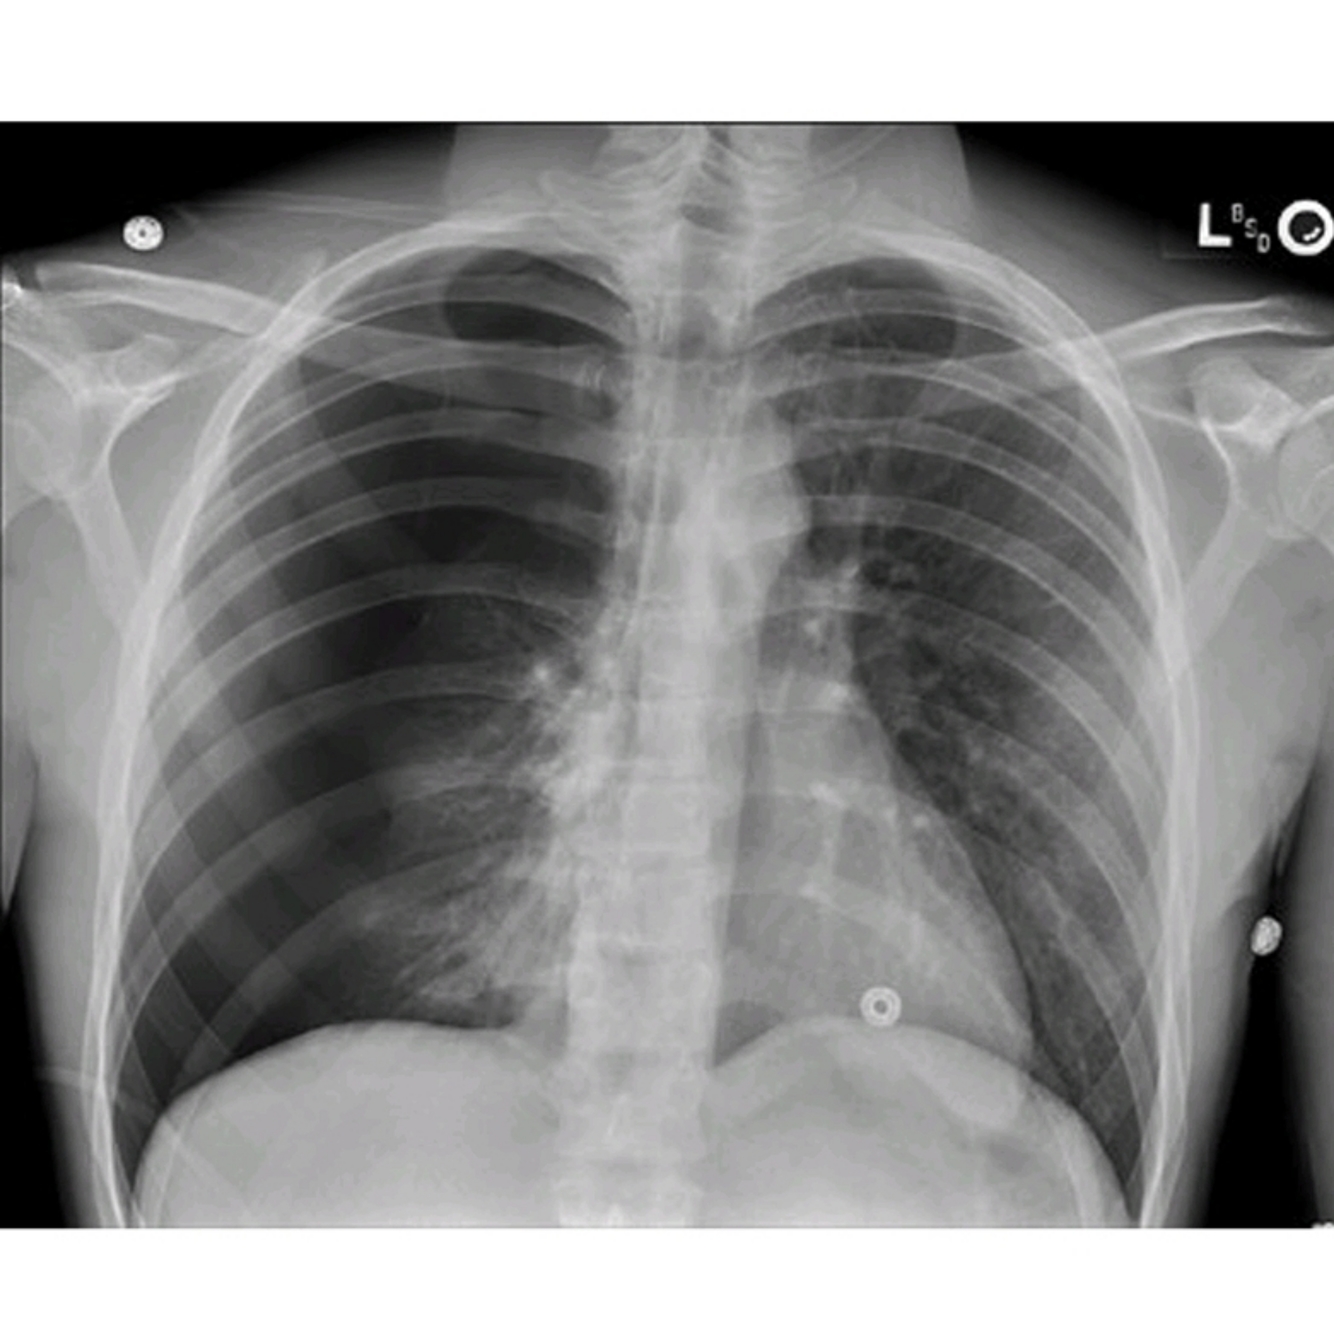

Name some causes for the changes seen in the image?

What’s the most valuable x-ray finding used to help differentiate the etiology of this finding

The most common causes of unilateral lung whiteout on chest radiograph (Fig. 45.1) are pneumonia, pleural effusion (including hemothorax), and collapse/atelectasis. The ability to differentiate between collapse and pleural effusion is essential beca

2. The most important finding that may help differentiate the etiology of unilateral whiteout is tracheal deviation or mediastinal shiftuse they require distinct treatments, which, if applied erroneously, could harm the patient [1].